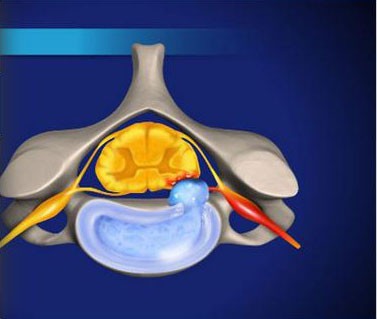

- Discography

- Lumbar Epidural Steroid Injection